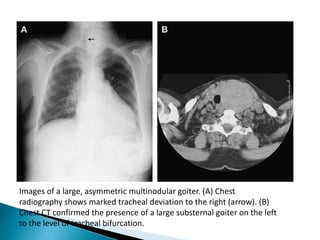

Images of a large, asymmetric multinodular goiter. (A) Chest

radiography shows marked tracheal deviation to the right (arrow). (B)

Chest CT confirmed the presence of a large substernal goiter on the left

to the level of tracheal bifurcation.